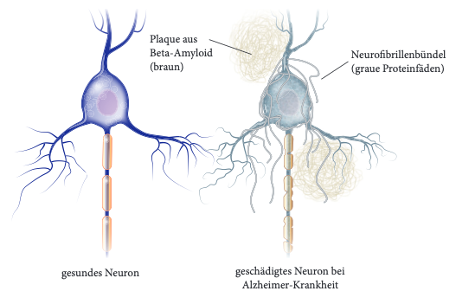

Alzheimer Pathogenese

Kritische Funktion des Hippocampus bei Konsolidierung

Synaptische Konsolidierung: Schneller Prozess im Hippocampus

System Konsolidierung: Transfer in den Neokortex als Langzeit-Prozess